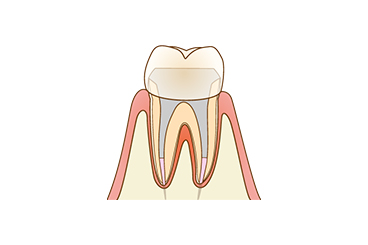

C3 神経に達した虫歯

虫歯が神経にまで達した状態です。何もしていなくても常に激しい痛みがあるため、早めの治療が必要です。 | 虫歯菌によって汚染された神経を除去する「根管治療」という治療を行い、被せ物で歯の見た目と機能を補います。 |

Root根管治療で神経まで進行した

虫歯が進行して歯が溶かされていくと、歯の神経まで感染してしまいます。ここまで進行すると常に激しい痛みが出るようになり、歯を削るだけでは対処できません。この状態の歯を放置すると、歯の神経は死んでしまって、最終的には歯が抜け落ちてしまいます。

何もしなくても歯が激しく痛む場合、適切な治療法になるのが歯の神経を除去する「根管治療」です。根管治療を行うことで、重度の虫歯になった場合でも抜歯せずに残せる可能性が出てきます。

歯を抜かないための「根管治療」

「根管(こんかん)」とは、歯の神経が入っている細くて複雑な形状の管のことです。根管内が虫歯菌に感染してしまうと、激しい痛みが出るだけでなく歯が抜け落ちてしまうこともあります。根管治療では、歯を残すために根管内の感染した神経や歯質を除去し、消毒する処置を行います。